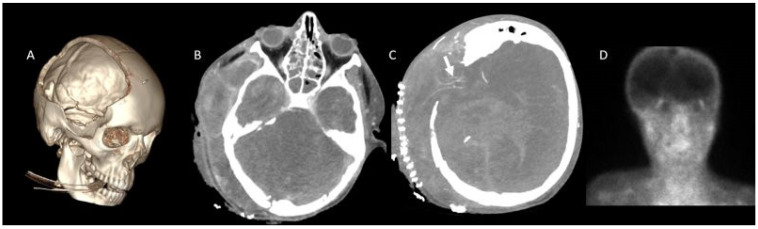

Background/objectives: While ancillary tests for brain death diagnosis are not routinely recommended in guidelines, they may be necessary in specific clinical scenarios. Computed tomography angiography (CTA) is particularly advantageous in pediatric patients due to its noninvasive nature, accessibility, and rapid provision of anatomical information. This study aims to assess the diagnostic sensitivity of a revised venous system (ICV-SPV) utilizing a 4-point scoring system in children clinically diagnosed with brain death.

Materials and methods: A total of 43 pediatric patients clinically diagnosed with brain death who underwent CTA were retrospectively analyzed. Imaging was performed using a standardized brain death protocol. Three distinct 4-point scoring systems (A20-V60, A60-V60, ICV-SPV) were utilized to assess vessel opacification in different imaging phases. To evaluate age-dependent sensitivity, patients were categorized into three age groups: 26 days-1 year, 2-6 years, and 6-18 years. The sensitivity of each 4-point scoring system in diagnosing brain death was calculated for all age groups.

Results: The revised venous scoring system (ICV-SPV) demonstrated the highest overall sensitivity in confirming brain death across all age groups, significantly outperforming the reference 4-point scoring systems. Furthermore, the ICV-SPV system exhibited the greatest sensitivity in patients with cranial defects.

Conclusions: The revised 4-point venous CTA scoring system, which relies on the absence of ICV and SPV opacification, is a reliable tool for confirming cerebral circulatory arrest in pediatric patients with clinical brain death.